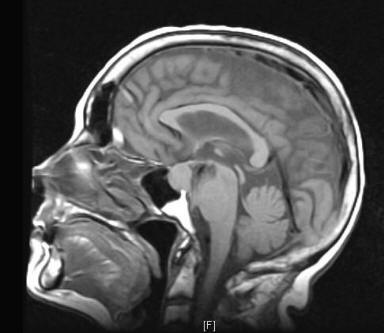

Pituitary Macroadenoma - Advanced Radiology Teaching

Pituitary Macroadenoma Joseph Junewick, MD FACR 08/13/2010 History 12 year old female with headache and visual disturbance. Diagnosis Pituitary Macroadenoma ... Doc Viewer